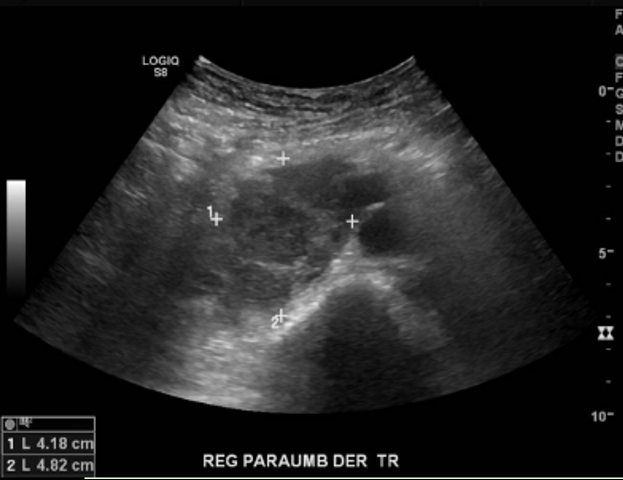

En la cavidad abdominal, en el área de la FID se aprecia una gran masa alargada y hipoecogénica multifocal, que ocupa todo el flanco y la fosa ilíaca derecha y que mide al menos 20 cm en sentido longitudinal, siguiendo la dirección del colon.

Los grandes vasos bien diferenciados. Múltiples adenopatías en el retroperitoneo y en el mesenterio.